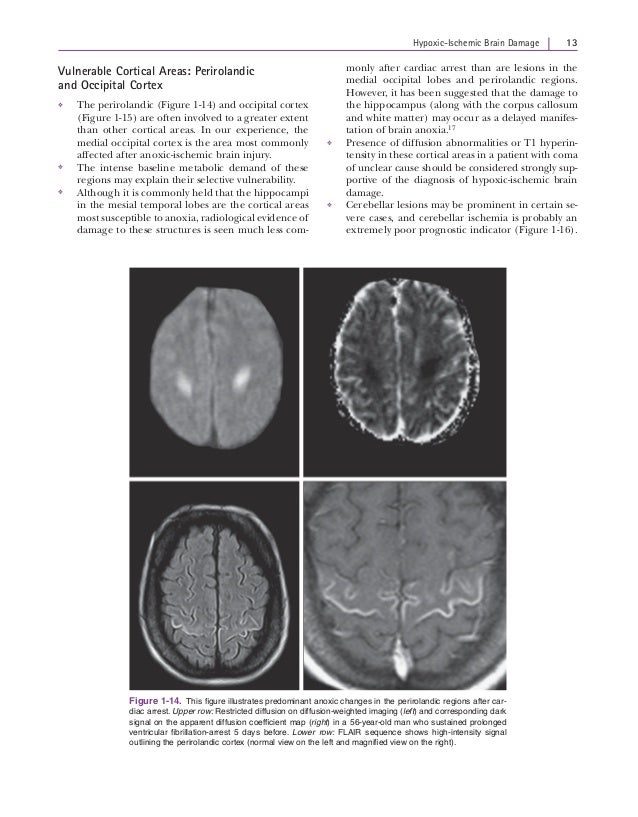

Hypoxic-ischaemic brain Injury - Practical Neurology

Hypoxic-ischaemic brain injury meaningful functional recovery but also guidance on management and, often, a con-tribution to communication with relatives. Although the assessment remains primarily prevent secondary cerebral damage due to hypotension. ... Get Content Here